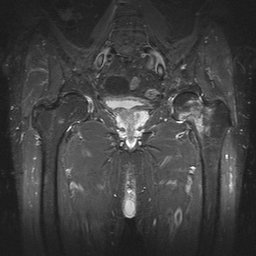

- Click on the image for a larger versionCCoronal MRI. This STIR sequence image shows intense signal in the left femoral neck region, due to fracture much more extensive than that predicted by the radiograph. This was a Garden II fracture.